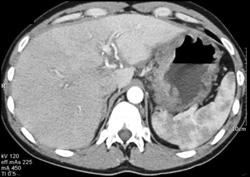

Colon Cancer Invades the Stomach